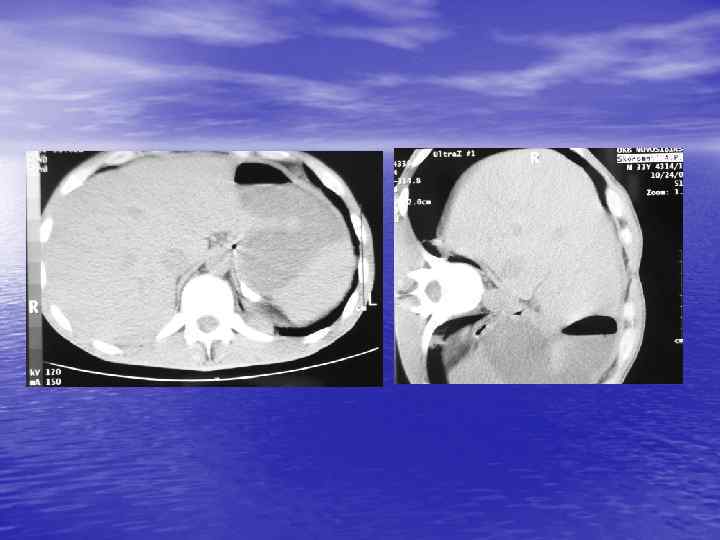

Денситометрический анализ Определение основных видов патологических образований: - обызвествленных - мягкотканных - жидкостных - жиросодержащих - воздухсодержащих

Денситометрия